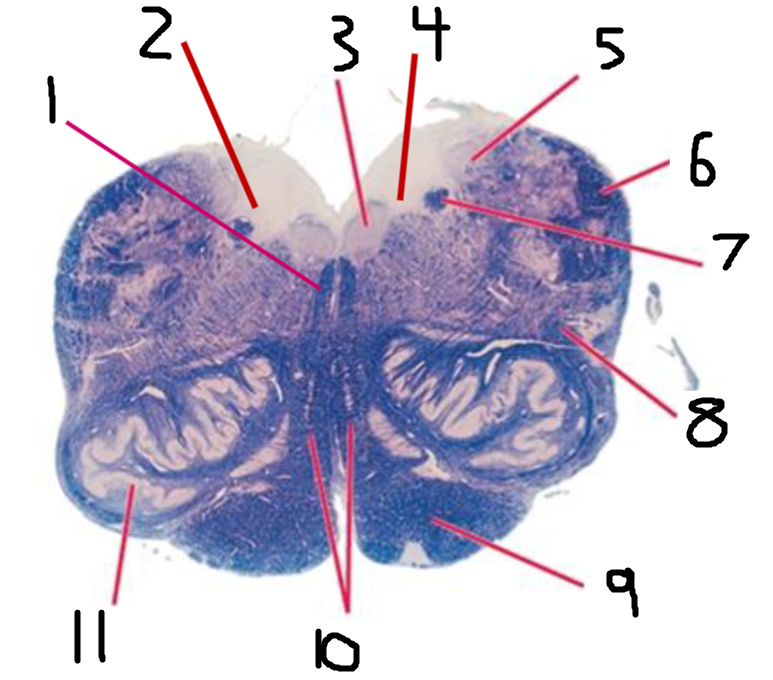

#1 is the:

Cingulate Gyrus

#2 is the:

Septum Pellucidum

#3 is the:

Lateral Ventricle

#4, #7, and #12 is the:

Fornix

#5 is the:

Third Ventricle

#6 is the:

Anterior Commissure

#8 and #11 is the:

Amygdala

#9 is the:

Hypothalamus

#10 is the:

Mammillary Body

#13 is the:

Insula

#14 is the:

Globus Pallidus

#15 is the:

Putamen

#16 is the:

Internal Capsule

#17 is the:

Caudate

#18 is the:

Corpus Callosum